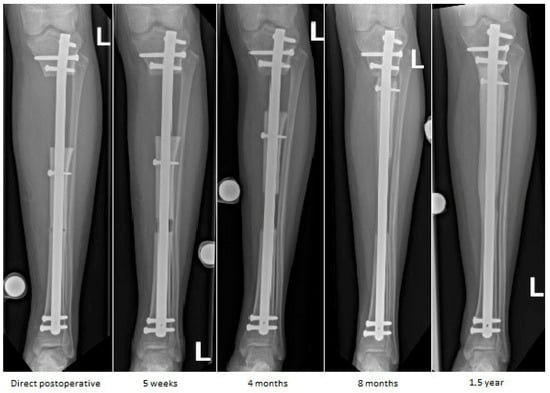

At 18 months postoperatively, radiographs confirmed complete consolidation at both the docking and distraction sites (Figure 7). At two years postoperatively, complete hardware removal was performed (Figure 8).

Figure 7.

Radiographs at 18 months follow-up showing anteroposterior view (left) and lateral view (right) of the tibia. Consolidation can be observed, demonstrated by bridging callus across cortices and the absence of visible fracture lines, with restoration of tibial alignment.

Figure 8.

Radiographs following hardware removal, showing anteroposterior view (left) and lateral view (right) of the tibia. Slight procurvatum and varus alignment are noted.